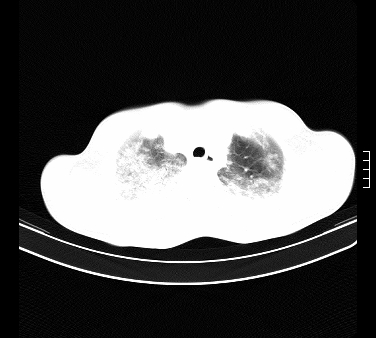

标题: CT15133:M17Y,百草枯中毒患者,典型病例分享 [打印本页]

标题: CT15133:M17Y,百草枯中毒患者,典型病例分享

患者,男,17岁,系我院急诊科收治的一例百草枯中毒患者,做ct检查时,距离服药的时间为3天。上传与大家分享

补充:百草枯进入人体内主要分部于肺和骨骼,肺部损伤24小时内出现水肿,2-3天内出现急性呼吸窘迫综合征,1-2周内出现肺纤维化。(引自陈灏珠,实用内科学12版)

不错,挺好。符合呼吸窘迫综合征